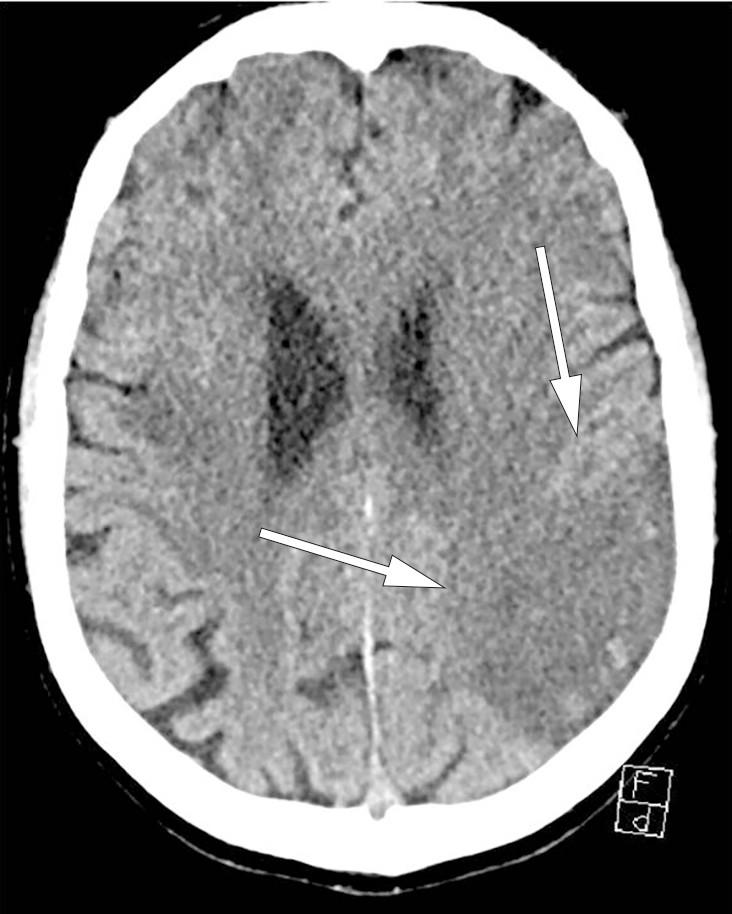

Ved undersøkelse i akuttmottaket hadde pasienten ekspressiv og impressiv afasi, pareser og styringsvansker i høyre arm og ben og nedsatt sensibilitet i høyre kroppshalvdel. NIHSS-skår var 8. CT caput viste ingen sikre infarktforandringer, og CT-angiografi viste ingen stenoser eller tromber. Han ble behandlet med actilyse omtrent to timer etter symptomdebut og 21 minutter etter at han kom til sykehuset. Kontroll-CT tatt neste dag viste forandringer forenlige med et ferskt infarkt i forsyningsområdet til venstre a. cerebri media (fig 1).

Figur 1 Kontroll-CT caput tatt 26 timer etter symptomdebut viser diffust avgrenset område med lavattenuasjon og utvisket…

Figur 1 Kontroll-CT caput tatt 26 timer etter symptomdebut viser diffust avgrenset område med lavattenuasjon og utvisket differensiering mellom grå og hvit substans og overflaterelieff, tilsvarende bakre forsyningsområde til venstre a. cerebri media, forenlig med etablert hjerneinfarkt